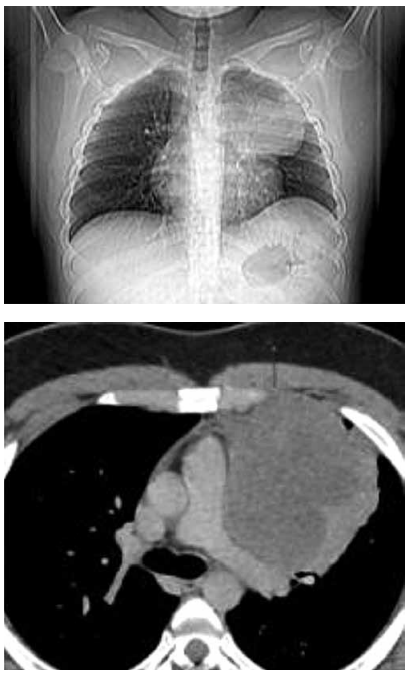

Observe a imagem a seguir:

(Arquivo pessoal; imagem usada com autorização)

A imagem mostra um exame de tomografia de tórax que demonstra espessamento pleural > 1,0 cm, difuso, irregular e que se estende à pleural mediastinal, com envolvimento do plano cissural e com redução de volume do hemitórax comprometido.

O quadro é fortemente sugestivo de